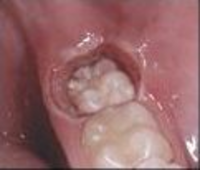

Ínnyel fedett bölcsességfog

Rádiósebészeti módszerrel felszabadított bölcsességfog